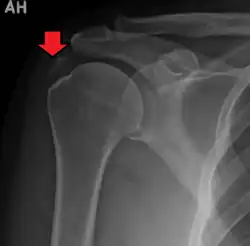

| A plain X ray of the shoulder showing calcific tendinitis | |

Calcific tendinitis is a common condition where deposits of calcium phosphate form in a tendon, sometimes causing pain at the affected site. Deposits can occur in several places in the body, but are by far most common in the rotator cuff of the shoulder. Around 80% of those with deposits experience symptoms, typically chronic pain during certain shoulder movements, or sharp acute pain that worsens at night. Calcific tendinitis is typically diagnosed by physical exam and X-ray imaging. The disease often resolves completely on its own, but is typically treated with non-steroidal anti-inflammatory drugs to relieve pain, rest and physical therapy to promote healing, and in some cases various procedures to breakdown and/or remove the calcium deposits.

Calcific tendinitis is typically diagnosed by physical examination and X-ray imaging.[1] During the formative phase, X-ray images typically reveal calcium deposits with uniform density and a clear margin.[1] In the more painful resorptive phase, deposits instead appear cloudy and with unclear margins.[1] By arthroscopy, formative stage deposits appear crystalline and chalk-like, while resorptive stage deposits appear smooth resembling toothpaste.[1] Ultrasound is also used to locate and assess calcium deposits. In the formative stage, deposits are hyperechoic and arc-shaped; in the resorptive stage deposits are less echogenic and appear fragmented.[1][3]